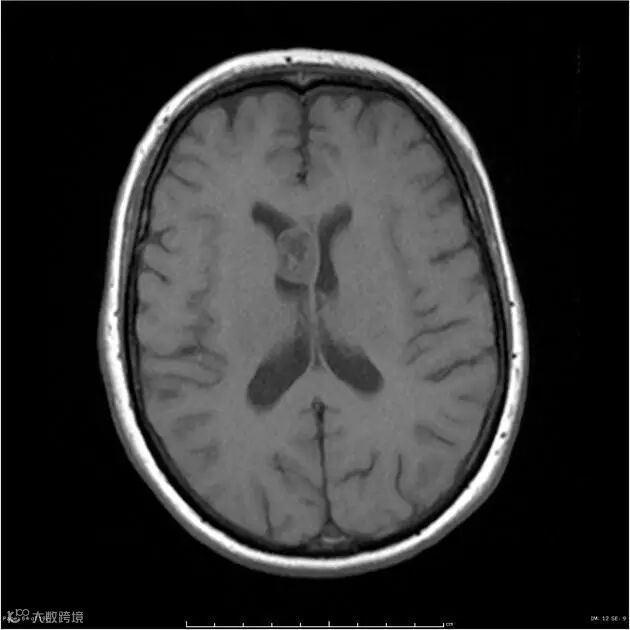

TIWI